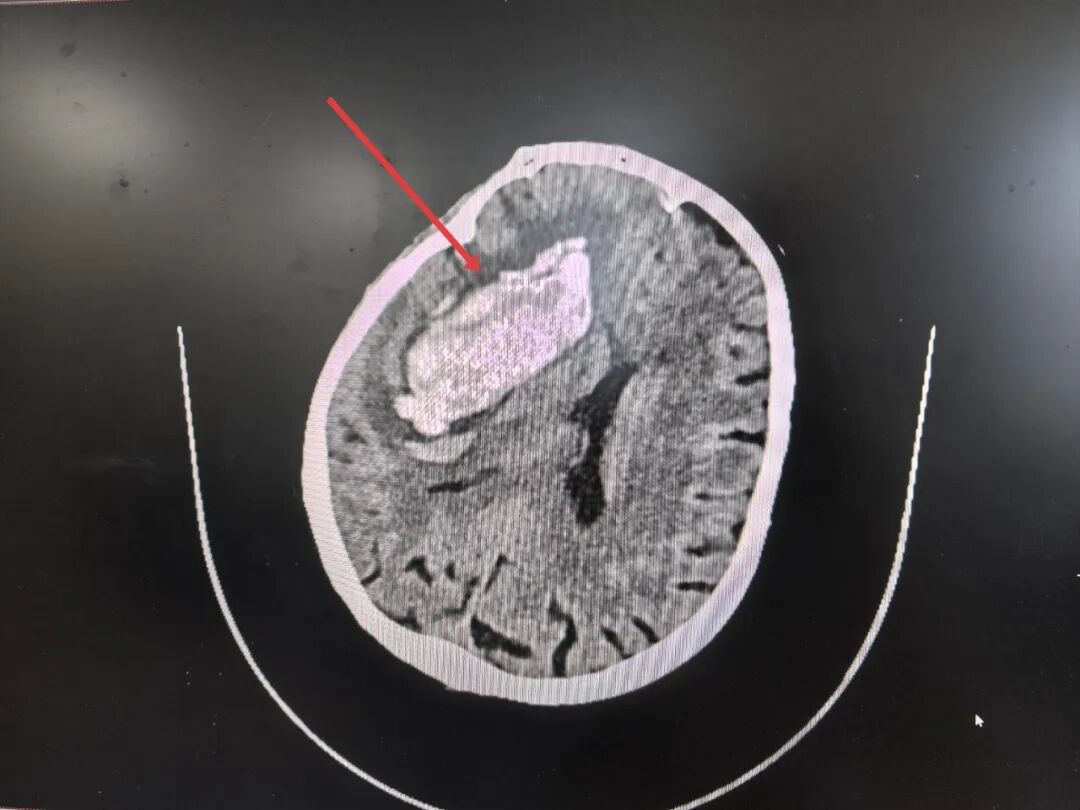

89岁老人命悬一线!市中山医院微创颅内手术成功救治高血压脑出血危重患者

2025年4月5日早晨八点左右,一位89岁的患者被紧急推入玉溪市中山医院危急重症中心。她意识丧失,陷入昏迷,不能对答,查体无法配合,随行的家属声音颤抖:“她有高血压好多年了,今早突然就……就喊不醒了!”紧急CT扫描结果令人倒吸一口凉气:梁奶奶右侧基底节区(大脑深处要害区域)大量出血,脑疝形成,血块体积巨大,形如“铸型”压迫着脆弱的生命中枢,中线结构被挤压得严重偏移——这是典型的高血压脑出血,且已发展到致...